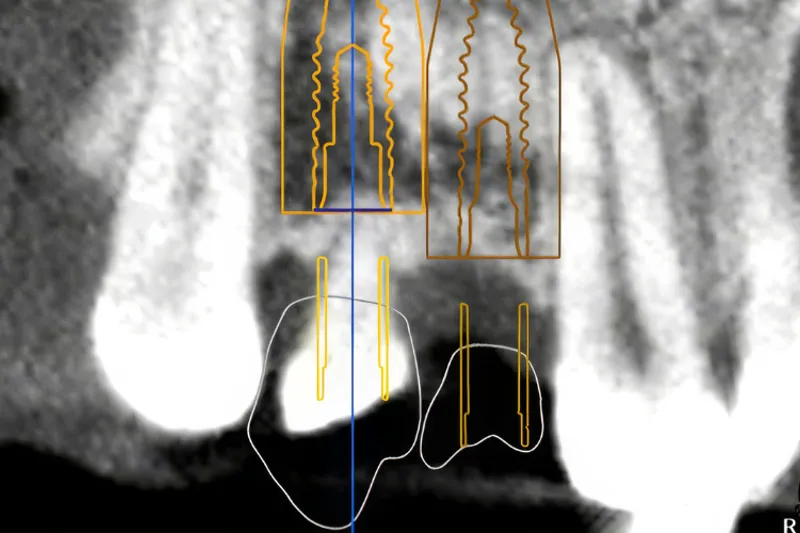

Tilstrækkelig højde og bredde af processus alveolaris er en forudsætning for at opnå en optimal tredimensionel implantatplacering og etablere grundlaget for en korrekt æstetisk og funktionel udformning af den efterfølgende protetiske rekonstruktion med en god langtidsprognose. Prøvetandsopstilling og styreskinner kan anvendes for at hjælpe til en optimal implantatplacering. Udvikling af softwareprogrammer har gjort det muligt at simulere den endelige protetiske rekonstruktion og implantatplacering samt udforme styreskinner, der intraoperativt kan assistere til udboring af implantatlejet og implantatindsættelsen. Imidlertid er guidet implantatindsættelse behæftet med risiko for fejl i forbindelse med databearbejdning, behandlingsplanlægning, printtekniske faktorer og intraoperativ forskydning af styreskinnen, som hver især kan have afgørende betydning for præcisionen af implantatbehandlingen. Implantatets placering anbefales derfor med en sikkerhedsmargin på 2 mm til nærliggende anatomiske strukturer og nabotænder. Guidet implantatindsættelse baseres på en grundig vurdering af patientens individuelle behov, behandlingens kompleksitet, anatomiske overvejelser og behandlerens erfaring og ekspertise med teknologien. Denne oversigtsartikel beskriver de digitale arbejdsgange ved planlægningen og udførelse af guidet implantatindsættelse ved hjælp af individuelt fremstillede styreskinner i to udvalgte patienttilfælde.

Sufficient height and width of the alveolar process is a prerequisite to ensure an optimal three-dimensional implant placement for a correct aesthetic and functional design of the subsequent prosthetic reconstruction with a good longterm prognosis. A dental mock-up and surgical guide can be used to assist in optimal implant placement. Furthermore, emerging of software programs has made it possible to simulate the final prosthetic reconstruction and implant placement, as well as the design of guide templates that can assist during implant bed preparation and implant placement. Guided implant surgery is associated with a risk of errors in data processing, treatment planning, technical printing conditions, and intraoperative displacement of the guide, each of which can have a crucial impact on the precision of the implant placement. Therefore, implant placement should be planned with a safety margin of 2 mm to adjacent anatomical structures and teeth. Guided implant surgery should be based on a thorough assessment of the patient's individual needs, the complexity of the treatment, anatomical considerations, and the clinician's experience and expertise with the technology. This article describes an overview of the digital workflow in the planning and execution of guided implant placements using individually manufactured guides in two selected patients.